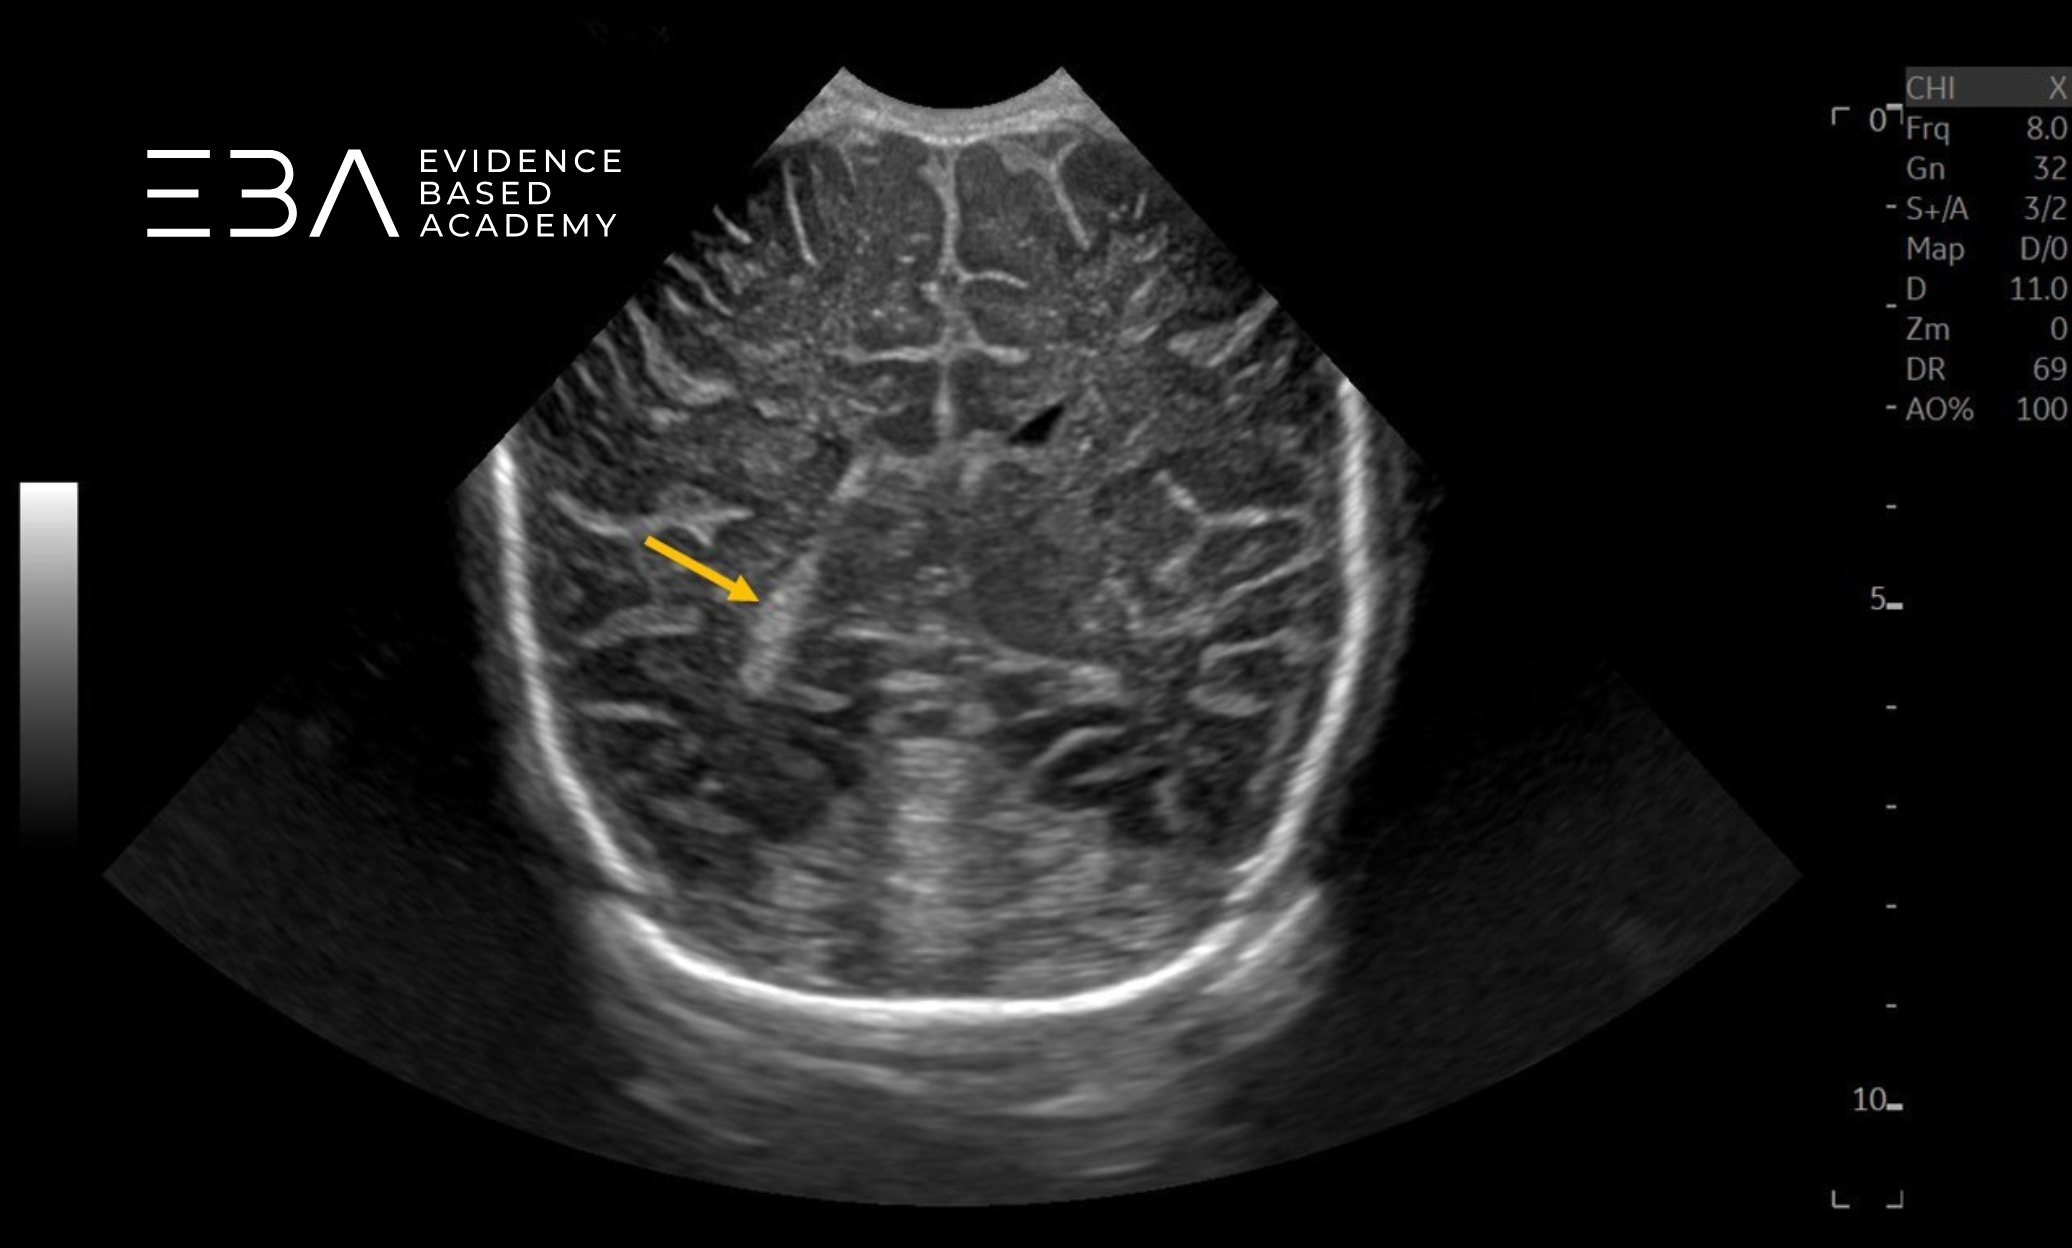

zdj. 11

Głowica mikrokonweksowa. Szczelina podłużna mózgu (niebieska strzałka), rogi czołowe komór bocznych (żółte strzałki), ciało modzelowate (fioletowa strzałka), jądra podstawy (zielone strzałki), śródmózgowie (czerwona strzałka).